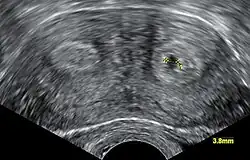

Transvaginal ultrasonography showing a cross-section of a bicornuate uterus, with two cavities (or "horns") to the left and right, respectively. The one to the right contains a gestational sac.

Diagnosis of bicornuate uterus typically involves imaging of the uterus with 2D or 3D ultrasound, hysterosalpingography, or magnetic resonance imaging (MRI). On imaging, a bicornuate uterus can be distinguished from a septate uterus by the angle between the cornua (intercornual angle): less than 75 degrees in a septate uterus, and greater than 105 degrees in a bicornuate uterus. Measuring the depth of the cleft between the cornua (fundal cleft) may also assist in diagnosis; a cleft of over 1 centimetre (0.39 in) is indicative of bicornuate uterus.[2]